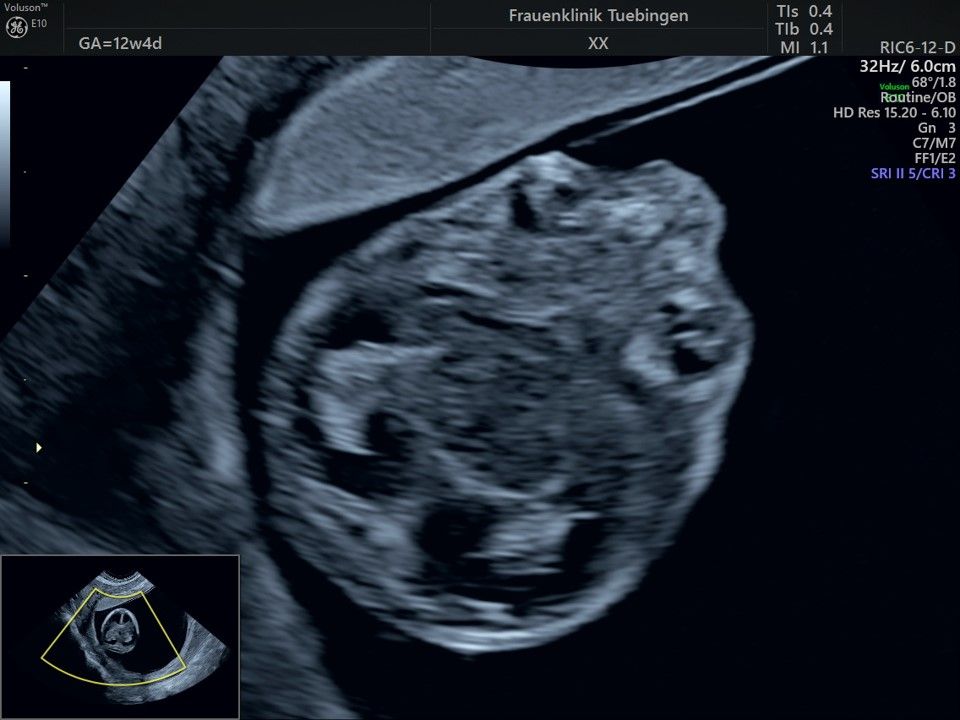

Im Rahmen des Ersttrimester-Screenings untersuchen wir die Organe des Feten mittels Ultraschall. Dabei machen wir auch gerne ein Bild für Sie.

Obwohl der Fet zu diesem Zeitpunkt erst zwischen 5 und 8cm groß ist, lassen sich bereits etwa die Hälfte aller schwerwiegenden Fehlbildungen erkennen bzw. ausschließen. Sollten wir eine Auffälligkeit sehen, werden wir mit Ihnen den Befund und das weitere Vorgehen ausführlich besprechen.

Fetale Anatomie

Herz

Bauchwanddefekt